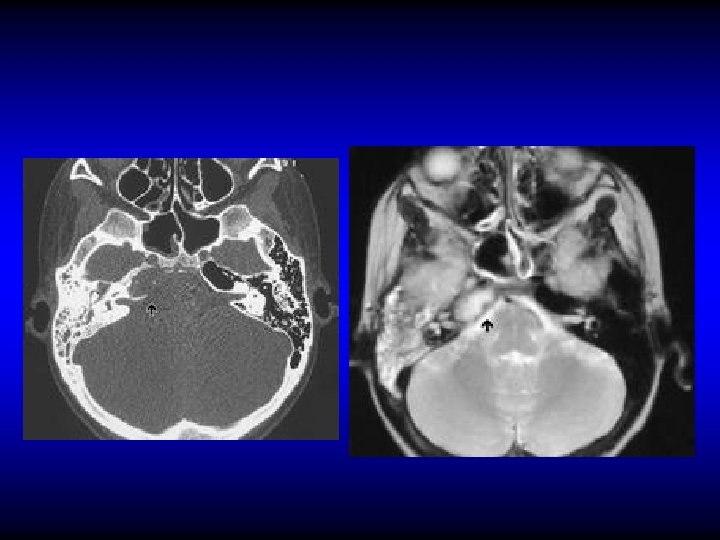

Pathology of labyrinthitis • Labyrinthine fistula – Erosion of the bony labyrinth usually due to cholesteatoma – Mostly in the lateral SCC • Acute labyrinthitis

Diagnosis of labyrinthine fistula • May be asymptomatic • Vertigo • SNHL • Fistula test • CT scan

Treatment of labyrinthine fistula • Mastoidectomy and surgical repair